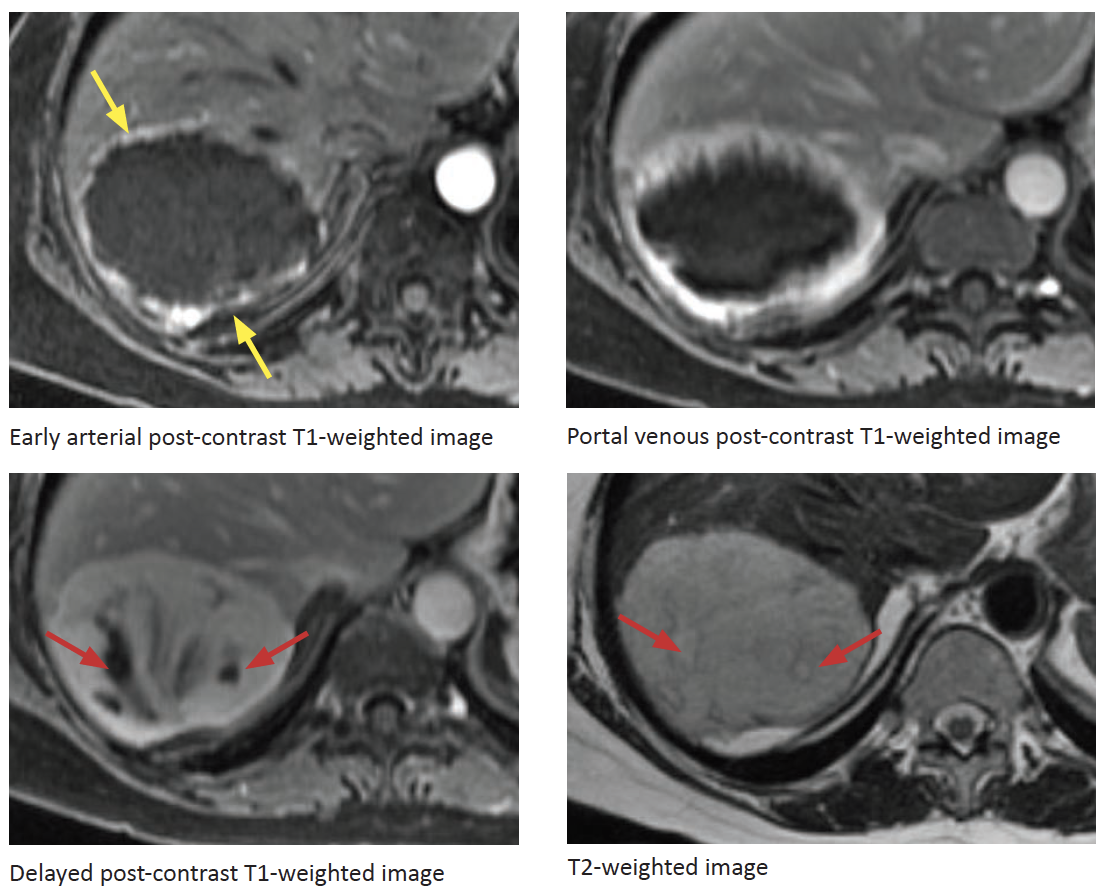

Dx?

Hemangioma

Note the two areas of nonehnacement on the delayed images consistent with cystic degeneration